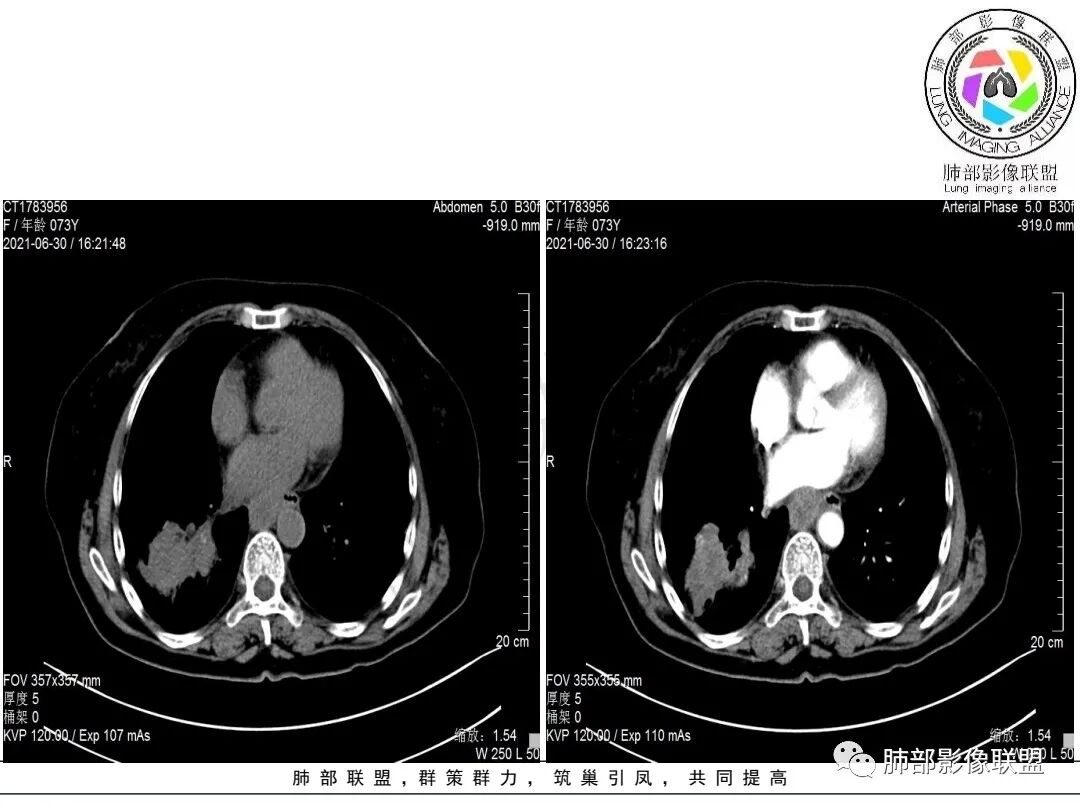

右肺下叶指套样高密度影,边界清楚,形态欠规则,累积多个叶段,平扫密度均匀,增强扫描不均匀强化,后纵隔淋巴结肿大,淋巴结内可见不均匀坏死,强化,女性,73岁,无实验室指标,考虑恶性:腺癌,鳞癌?神经内分泌癌(大细胞?),淋巴上皮瘤样癌。加一个转移瘤。

右肺下叶不规则形肿块,密度不均,轻度强化,纵隔肺门肿大淋巴结,里面血管好像破坏了,考虑恶性,鳞癌?鉴别结核。

右下肺肿块,多发浅分叶呈锯齿状,有指样突起和胸膜牵拉,不均匀强化,肿块内血管增粗模糊,后纵隔淋巴结肿大坏死融合呈冰冻状,定性恶性,低分化腺癌>小细胞肺癌。

老年女性,有桶状胸,长期吸烟?右肺下叶占位并纵膈7组,肺门10组淋巴结明显肿大融合,有不均匀性强化,肺内可见下叶支气管外压性狭窄,管腔近段感觉支气管没有影响,整体病灶成支气管走形,边界清楚,考虑恶性可能性大,小?

考虑小细,纵膈及右侧肺门淋巴结肿大并左下肺小叶间隔增厚,提示周围及中央淋巴管转移,左心房及左下肺静脉受累。

右肺下叶不规则肿块,纵隔及右侧肺门淋巴结肿大,不均匀强化,见坏死,考虑恶性,小细胞癌或鳞癌。

女,73,咳嗽2月。

胸部CT:桶胸,肺气肿背景,右下肺不规则肿块影,沿支气管血管束生长,边界较清,边缘毛糙、锯齿样,基底干支气管腔内隆起,部分支气管进入后堵塞。平扫密度较均匀,轻度强化,肿块内血管增粗模糊,7区淋巴结肿大明显,内见小片坏死,左房受侵,邻近胸膜增厚。考虑恶性,低分化腺?鳞?鉴别TB、PC等。

1.老年女性,咳嗽两月。CEA,T-spot阴性。

2.右肺下叶不规则实性密度块影,占据外后基底段及背段较大范围,可见轻度分叶、毛刺及棘状突起,未见明显胸膜牵拉及凹陷。

3.右肺下叶支气管轻度狭窄,病灶内见部分充气支气管征,外后基底段不能连续跟踪。

轻度不均匀强化,病灶内小血管显示不满意,未见明确坏死区。

4.右肺门及纵隔见多处增大淋巴结,不均匀环形强化,后下纵隔(隆突下)肿大淋巴结十分显眼!